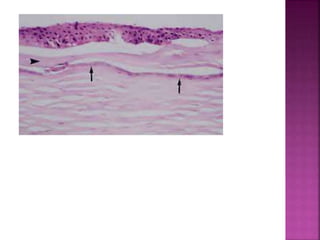

 epithelial denudation as shown above (arrow

1), destruction of Bowman’s layer(arrow2)

 epithelial denudationas shown above (arrow 1), destruction of Bowman’s layer(arrow2)